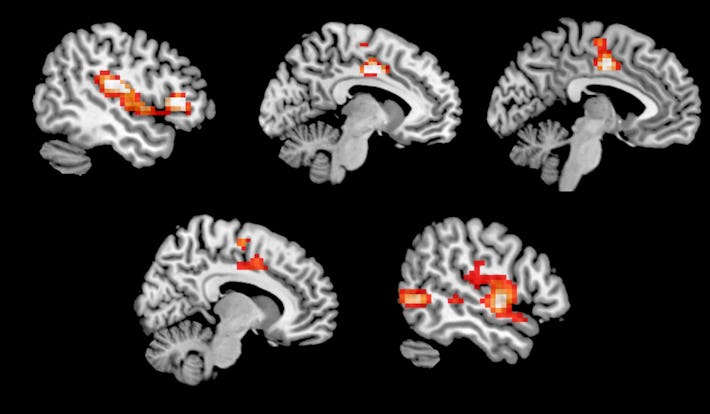

The orange represents areas of the brain that showed increased activity when on MDMA

Researchers believe the release of norepinephrine and dopamine contributes to the euphoria, and increased energy MDMA users feel, but that’s just the sideshow. The main event is the massive release of serotonin. Serotonin makes you feel good, as well as increases sensitivity to light, touch, and sound. You can see why music, lights, and face-stroking are commonplace at raves.

MDMA has been shown to acutely decrease activity in the left amygdala, an area associated with fear and memory, as well as increase blood flow to the prefrontal cortex (PFC) in the brain (the area involved in complex decision making and behavior). This reduction of activity in the amygdala might be one reason it’s been shown to be an effective treatment for people with PTSD.